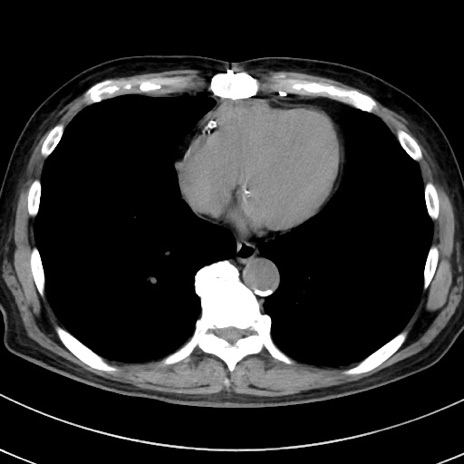

症例38(横断像)

【症例】70歳代 男性

【主訴】腹痛・嘔吐

【現病歴】昨晩より、嘔吐・腹痛あり。今朝になっても嘔吐あり。来院。

【既往歴】心臓バイパス手術、開腹胆摘、腸閉塞

【身体所見】BP 107/71mmHg、HR 116/min、腹部:平坦、軟、下腹部に軽度圧痛あり。反跳痛なし。

【データ】WBC 15100、CRP 0.32